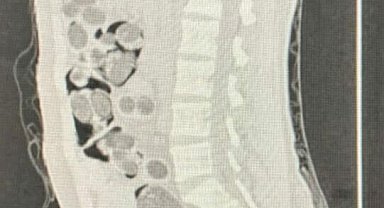

Yabancı uyruklu yolcunun midesinden 219 paket uyuşturucu çıktı